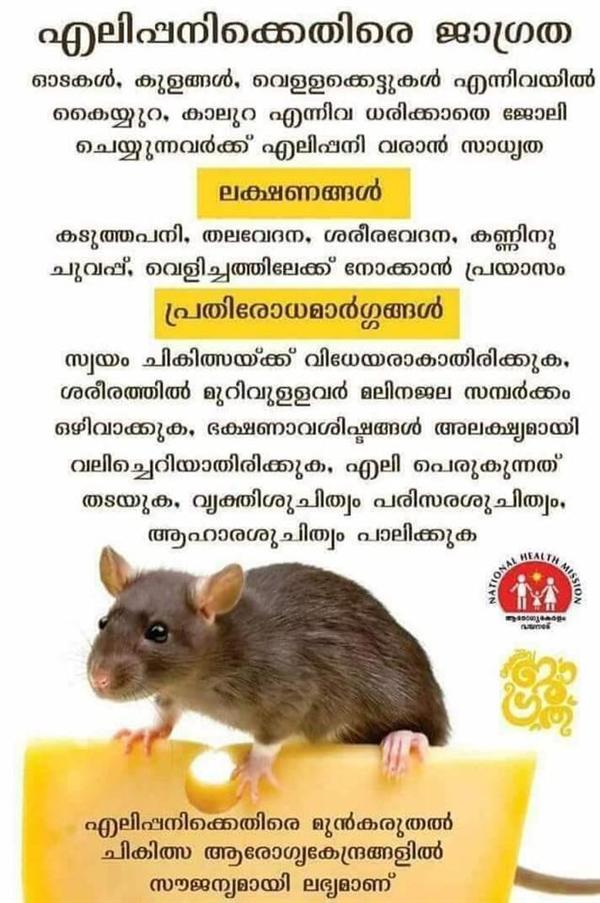

എലിപ്പനി അതിരുക്ഷമായിരിക്കുന്ന ഈ സമയത്ത് എല്ലാ ജനങ്ങളും മുൻകരുതലെടുക്കുക. Continue reading